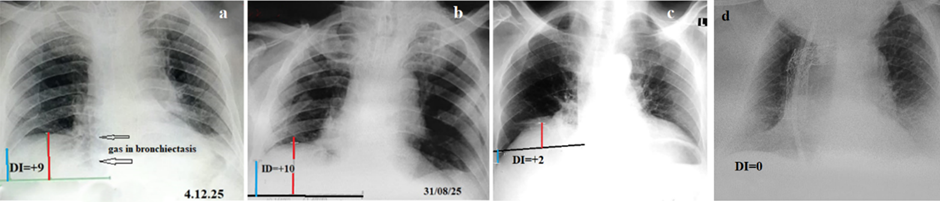

The diaphragmatic domes are anatomically attached to the tenth thoracic vertebra. During inspiration, the diaphragmatic domes descend, resulting in an increase in lung volume as air is drawn into the lungs. During expiration, the domes ascend, reducing lung volume by expelling air. This physiological relationship forms the basis for a quantitative assessment of lung volume using plain chest radiography. To determine the relative volume of the right lung, a horizontal reference line (baseline) was drawn on the chest radiograph along the lower edge of the tenth thoracic vertebra. Along the right midclavicular line, a perpendicular vertical line was drawn from the highest point of the right diaphragmatic dome to the baseline. If the dome was located above the baseline, the measured distance in centimeters was assigned to have a positive value; if below the baseline, a negative value was assigned. A second vertical line was drawn from the intersection of the baseline with the right lateral chest wall to the deepest point of the right costophrenic sinus. The length of this line was also measured in centimeters and assigned a positive or negative value depending on whether its upper end was located above or below the baseline. The diaphragmatic index (DI), representing an integral quantitative characteristic of right lung volume, was calculated as the sum of the diaphragmatic dome height and the sinus depth (Figure 1). Previous studies conducted in individuals without pulmonary pathology demonstrated that, under conditions of normal breathing, DI values range from 0 to +5 [5,6].

Figure 1. The principle of the proposed method. (a). Location of the diaphragm in a patient with a normal right lung volume. (b). Schematic for Figure 1.a. (c). In the chest radiograph the gas-filled bronchiectasis (arrows on the right) are visible. There are no shadows above the diaphragm, and no difference in diaphragmatic height on either side. However, the cardiac shadow is displaced to the left and rotated, as evidenced by the absence of the right hilus. (d). Atelectasis of the lower lobe on the right is visible against the liver shadow as a lighter triangular shadow (green line). The atelectasis occupies the same location as the bronchiectasis in Figure 1c. In both cases (c, d), the DI was greater than normal, indicating a decrease in the volume of the right lung.